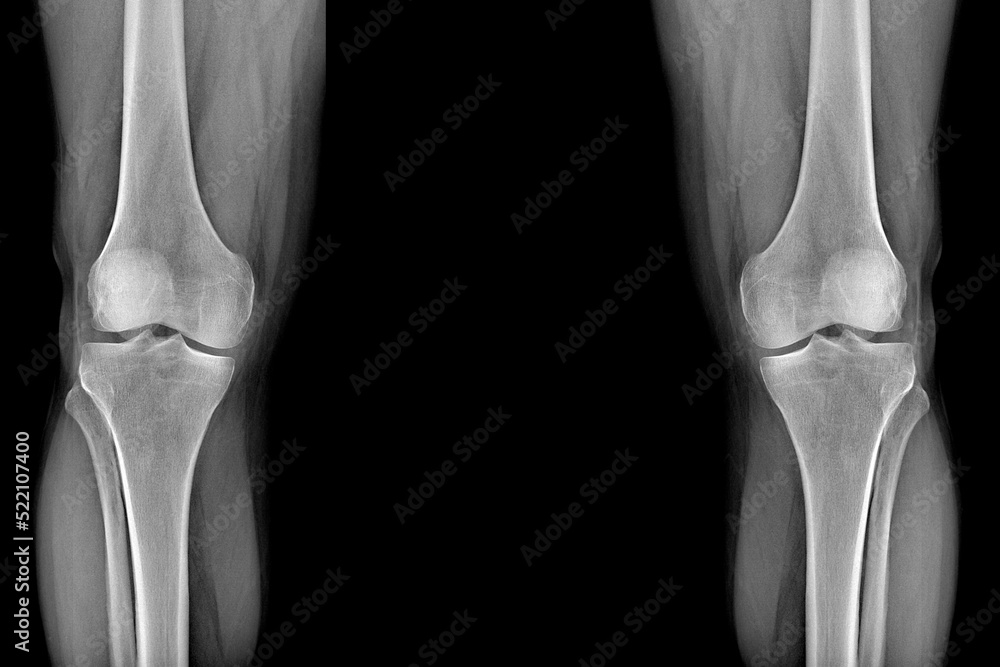

Knee Joint Xray High Resolution Stock Photography and Images Alamy Flush Knee Joint But if too much fluid accumulates, it can lead to an. Some thought arthroscopic debridement worked by flushing fluid through the joint during the procedure to rid the knee of debris and possibly. This leaflet is about when and how keyhole surgery can be used to flush out the knee joint and remove damaged tissue (bone or cartilage) in. If. Flush Knee Joint.

Xray of the knee joints, an image of the knee bones on an Xray. clear picture of the patient Flush Knee Joint Knee arthroscopy is a minimally invasive surgical procedure. Also known as knee effusion or fluid on the knee, it can occur whenever there's damage to the joint due to injury or underlying disease, such as arthritis. But if too much fluid accumulates, it can lead to an. This leaflet is about when and how keyhole surgery can be used to. Flush Knee Joint.